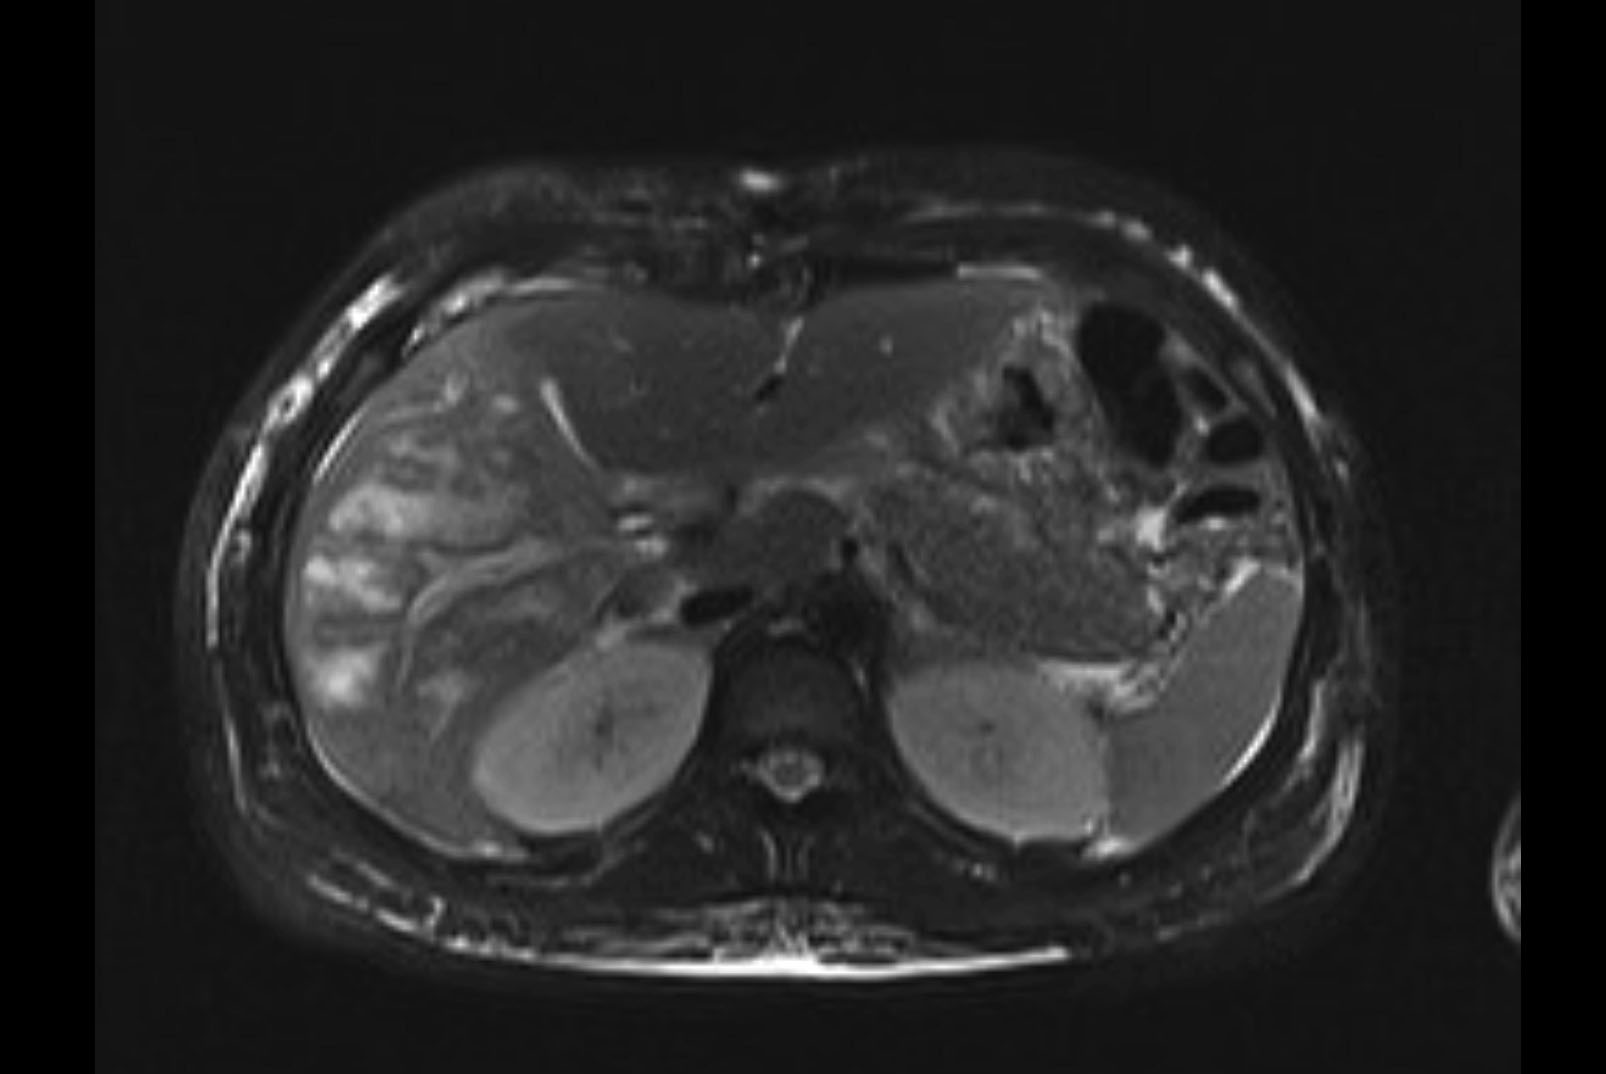

Imaging Analysis

Look through the patient's CT scan to identify any areas of concern for the necessary procedure.

MRI T1

Based on initial findings, which issue(s) would you be most concerned about?